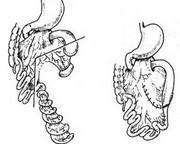

先天性小肠闭锁和肠狭窄

628健康网为您分享有关先天性小肠闭锁和肠狭窄的症状,先天性小肠闭锁和肠狭窄的治疗方法,先天性小肠闭锁和肠狭窄的预防...

先天性肠闭锁

628健康网为您分享有关先天性肠闭锁的症状,先天性肠闭锁的治疗方法,先天性肠闭锁的预防知识,先天性肠闭锁的症状图片,先...

环形胰腺

628健康网为您分享有关环形胰腺的症状,环形胰腺的治疗方法,环形胰腺的预防知识,环形胰腺的症状图片,环形胰腺吃什么药,环...